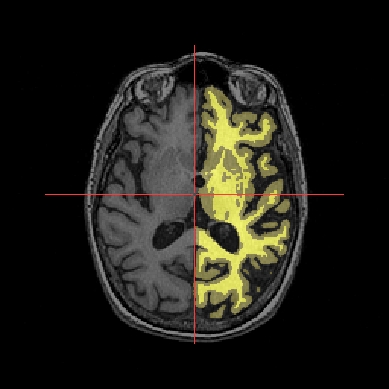

In the following example, 3 objects are loaded in Anatomist:

Object1 (O1): anatomy

Object2 (O2): regions of interest graph drawn from the anatomy. So these 2 objects are in the same referential.

Object3 (O3): nomenclature to associate colors to regions of interest according to their name. This object does not have to be put in a window. Link between names in the nomenclature and in regions of interest is done automatically by Anatomist.

These 2 objects are in the same coordinates system, so they will be placed in the same referential, that is to say they will have the same color circle (red by default).

Superimposing an anatomy and regions of interest¶